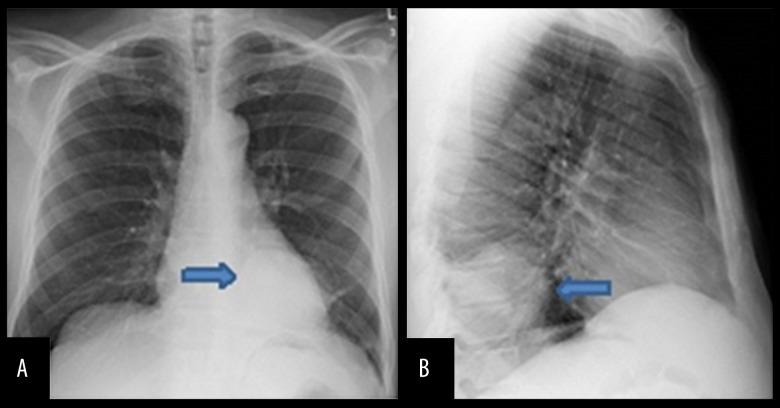

BACKGROUND Sarcomatoid carcinoma is a rare, aggressive, malignant cancer composed of sarcoma and sarcoma-like components, and can occur in different organs such as the thyroid gland, bone, skin, breast, pancreas, liver, urinary tract, and lung. Pulmonary sarcomatoid carcinoma accounts for only a small percentage of lung cancers and has histological variants that include pleomorphic carcinoma, giant cell carcinoma, spindle cell carcinoma, carcinosarcoma, and pulmonary blastoma. CASE REPORT Here, we present a case of sarcomatoid carcinoma in a 63-year-old HIV-positive Hispanic male who presented with back pain, dry cough, and weight loss. A CT scan of his chest showed an ovoid mass in the lower lobe of the left lung, and an MRI of the spine showed a left lateral paraspinal soft tissue mass causing central canal stenosis and mild cord compression. The patient underwent laminectomy and resection of the spinal mass. A transthoracic needle biopsy of the lung and spinal masses had similar histopathology, and were indicative of sarcomatoid carcinoma. CONCLUSIONS We report a rare case of sarcomatoid carcinoma involving both the lung and spinal cord in the same patient. Sarcomatoid carcinomas of the lung have poor prognosis and are aggressive cancers. Moreover, our case also had the co-occurrence of HIV and sarcomatoid carcinoma.

肉瘤样癌是一种罕见的侵袭性恶性肿瘤,由肉瘤和肉瘤样成分组成,可发生于不同器官,如甲状腺、骨骼、皮肤、乳腺、胰腺、肝脏、泌尿道和肺部。肺肉瘤样癌仅占肺癌的一小部分,具有多种组织学变异型,包括多形性癌、巨细胞癌、梭形细胞癌、癌肉瘤和肺母细胞瘤。病例报告:在此,我们报告一例63岁的HIV阳性西班牙裔男性肉瘤样癌患者,该患者出现背痛、干咳和体重减轻症状。胸部CT扫描显示左肺下叶有一个椭圆形肿块,脊柱MRI显示左侧椎旁软组织肿块,导致中央管狭窄和轻度脊髓受压。患者接受了椎板切除术和脊柱肿块切除术。对肺部和脊柱肿块进行的经胸针吸活检具有相似的组织病理学表现,提示为肉瘤样癌。结论:我们报告了一例罕见的同一患者同时发生肺和脊髓肉瘤样癌的病例。肺肉瘤样癌预后较差,是侵袭性癌症。此外,我们的病例还同时存在HIV和肉瘤样癌。